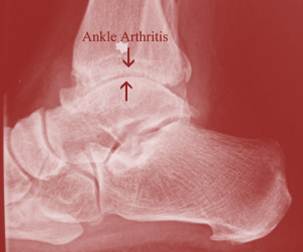

Ankle Arthritis

Ankle Instability – Chronic, repetitive sprains of the ankle. This can be due to an injury that never healed properly but can also be due to weak ankle ... Fetch Doc

Ankle Arthritis - About.com Health

Learn about foot and ankle arthritis and treatment of these conditions. Ankle arthritis is uncommon, but can cause significant pain when walking. ... Read Article

Ankle Osteoarthritis - Causes - Diagnosis - Symptoms ...

Osteoarthritis (OA) in the ankles can cause pain, stiffness, and other symptoms. Learn about ankle osteoarthritis causes, diagnosis, symptoms, pain relief, and treatment. ... Read Article

Osteoarthritis Of The Foot And Ankle - CT Ortho

Dr. David Caminear 203.407.3528 Osteoarthritis of the Foot and Ankle What Is Osteoarthritis? Osteoarthritis is a condition characterized by the breakdown and eventual loss of cartilage in ... Read Here

Arthritis Of The Foot And Ankle -LB - Footdr.com

Arthritis of the Foot and Ankle! Arthritis is the leading cause of disability in the United States. It can occur at any age, and literally means "pain within a joint." As a result, arthritis is a term used broadly to refer to a number of different conditions. ! ... Get Document